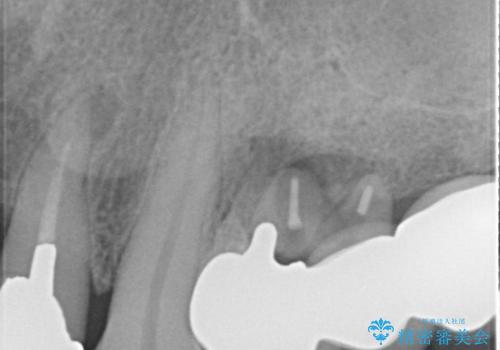

診察した結果、ブリッジの土台となっている歯が割れていたため、抜歯が必要となりました。

インプラントを埋入するために必要な骨の高さがなかったため、上顎洞底の粘膜を挙上しました。

手術後は処置部に痣や腫脹が出現したり、痛みが出たりしましたが、補綴治療後は咬み合わせが安定し、大変満足していただきました。